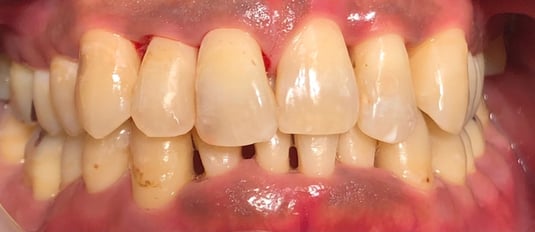

10月7日

歯石除去前です。